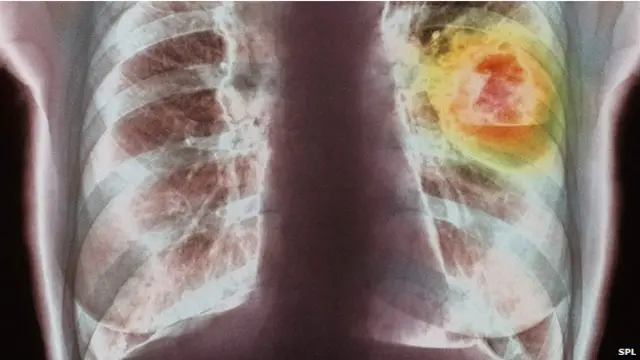

दुनिया भर में सबसे ज़्यादा कैंसर के मामले फेफड़े से संबंधित हैं जबकि दूसरा स्थान <link type="page"><caption> स्तन कैंसर</caption><url href="http://www.bbc.co.uk/hindi/international/2013/11/131129_health_cholesterol_rt.shtml" platform="highweb"/></link> का है.

हर साल सबसे अधिक मौतें भी फेफड़े के कैंसर से होती है.